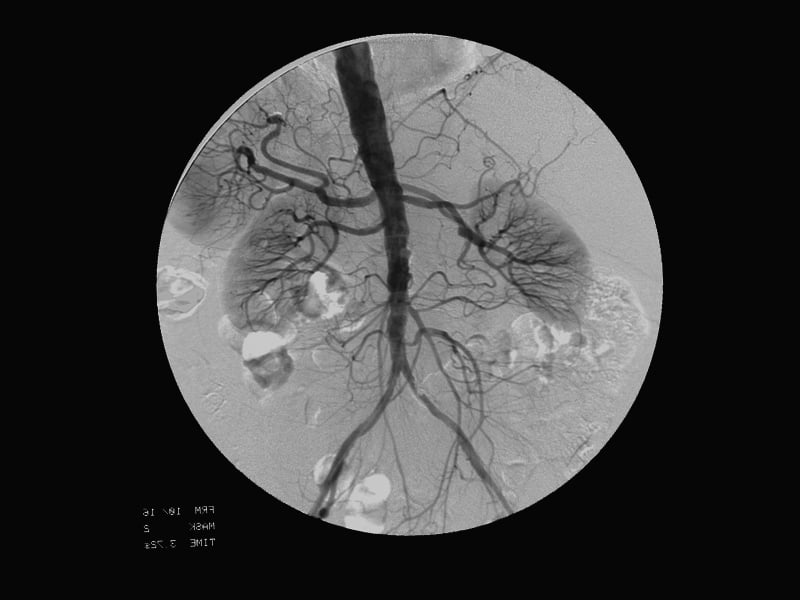

Cardiovascular-interventional procedures use sophisticated imaging techniques to help guide catheters, filters, stents, or other tools or devices through the body. Using these methods, diseases can be treated without surgery.

Cardiovascular-interventional image / Image © ASRT

Cardiovascular-interventional image